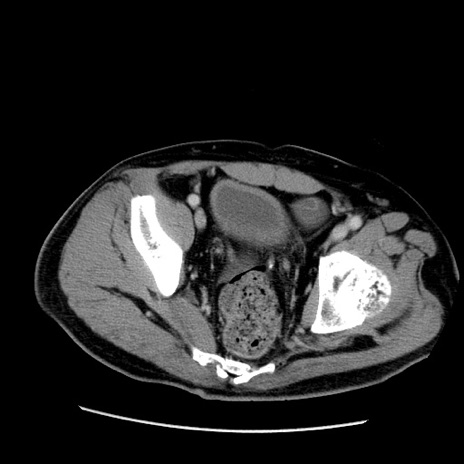

症例22(横断像)

【症例】50歳代男性

【主訴】腹痛

【現病歴】AVMからの被殻出血のため回復期リハ病棟入院中。 本日午後3時頃急に下腹部痛が出現した。

【既往歴】AVM、被殻出血、虫垂炎、高血圧

【身体所見】意識晴明、左半身不全麻痺、会話の理解は良好、36.5°C、腹部:膨隆、全体に板状硬、下腹部正中に圧痛点あり、反跳痛-、筋性防御不明、右下腹部にope scar

【データ】WBC 9400、CRP 0.06